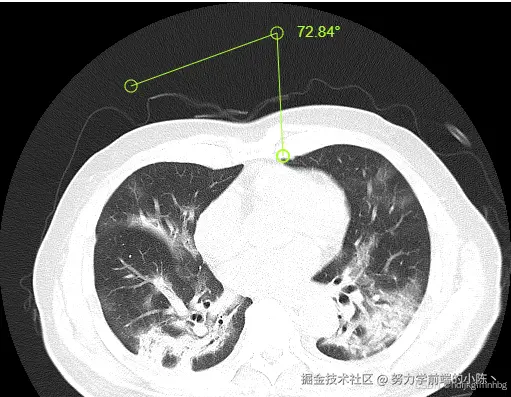

除了调整曝光度之外,cornerstone还给我们提供了很多操作例子,下面博主再演示一个例子:AngleTool,用来给测量并标记影像角度的工具

核心代码如下

// 添加工具

const AngleTool = cornerstoneTools.AngleTool

cornerstoneTools.addTool(AngleTool)

// 设置操作实现方式,mouseButtonMask是通过鼠标点击来操作,1的意思是点击鼠标左键实现

cornerstoneTools.setToolActive('Angle', {mouseButtonMask: 1})

其他代码不变,只将这一部分替换就好了

效果如下: